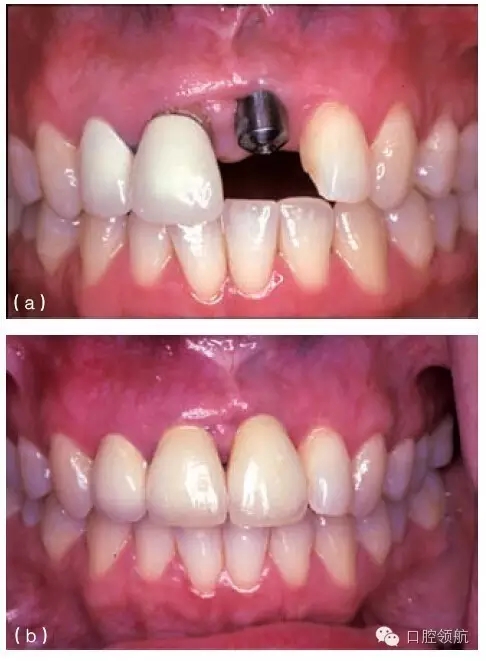

其他的美學(xué)問題與種植體植入位置不當(dāng)(圖10.20a,b),以及植入前存在骨吸收有關(guān)。骨吸收的存在使種植體無法植入到理想位置,造成單冠之間或是固定局部義齒的橋體之間存在頸部間隙(圖10.21)。

圖10.20 (a)中切牙種植體的位置太偏唇側(cè),采用定制的基臺盡可能補償頰側(cè)的錯位。(b)一并更換相鄰的兩個冠修復(fù)體以獲得更滿意的結(jié)果。

種植體植入太偏唇側(cè),將造成明顯的美學(xué)問題,而且通常很難克服(圖10.20a,b)。